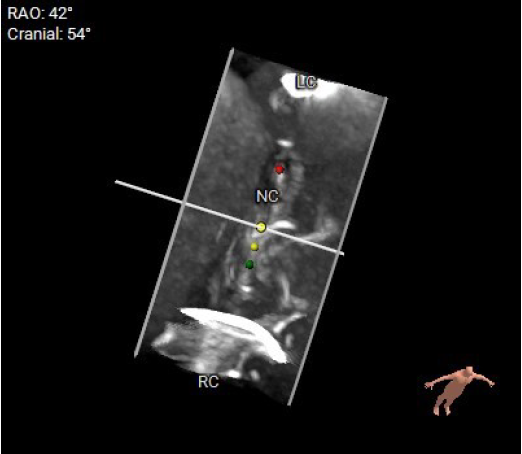

影像分析

生物瓣金属内径28.9mm

面积折算直径21.6mm

周长折算直径21.8mm

无论开展任何瓣位的瓣中瓣手术前,都应先明确原外科生物瓣的类型和型号,不同类型的外科生物瓣都具有不一样的透视下特征,如果透视性差的情况下,术中需要结合TEE协助定位。同样,原外科生物瓣的尺寸也对介入瓣尺寸的选择至关重要。

本例患者15年前因三尖瓣增厚伴重度反流,接受31#三尖瓣生物瓣置换。该类型的外科生物瓣在影像下透视性差,术中难以清晰捕捉其形态和位置。同时,其右心室狭小,留给介入瓣操作的空间有限,使得本次手术难度升级。宁波市第一医院心外科励峰主任团队凭借丰富的瓣膜外科手术经验,成功经右房途径TTViV植入一枚29#的J-Valve瓣膜。J-Valve经心尖介入瓣膜系统,在治疗生物瓣衰败的改为患者中行瓣中瓣植入术可以取得良好的临床效果。其独特的定位件设计,能够准确牢固地锚定在原生物瓣的瓣脚上,降低瓣膜移位的发生率。术后,患者三尖瓣跨瓣压差、反流及右房压均明显改善,即刻获益。